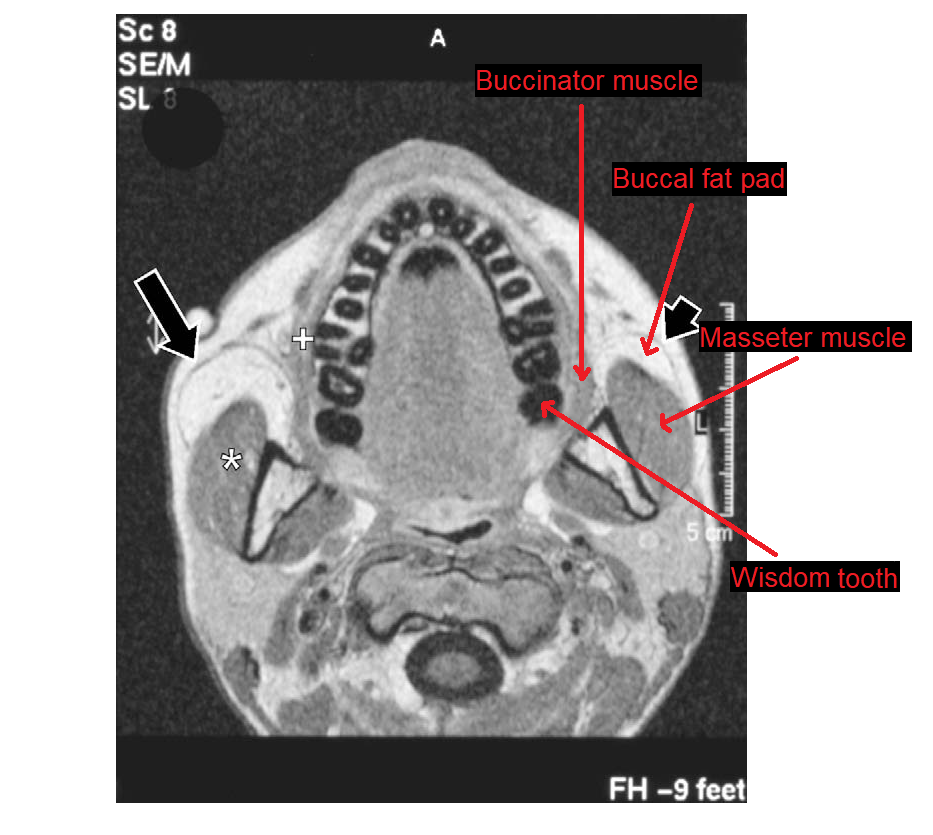

I as well, this year, found an MRI image online, an axial MRI of the human skull from which you can see that the third molars and the masseter muscles have tissue between them, and no gaps, and so that if they are removed, the masseter muscles would be affected, losing support and "collapsing". The picture is attached to this post.

As well, the picture shows that the buccal fat pads sit in the middle, between the buccinator muscles and the masseter muscles, and fill the gap, so to speak, between the wisdom teeth and the masseter muscles.

MRI axial of masseter m., bucal fat pad, bucciantor m. and third molar.png